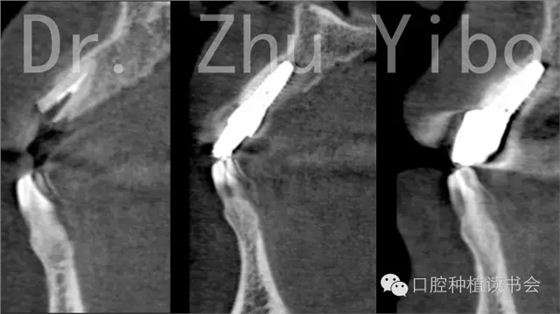

術(shù)前術(shù)后CBCT對(duì)比測(cè)量示:唇側(cè)牙槽骨穩(wěn)定(圖13)。術(shù)前術(shù)后石膏模型掃描,數(shù)字軟件重合對(duì)比測(cè)量:唇側(cè)牙齦組織穩(wěn)定(圖14)。

圖13